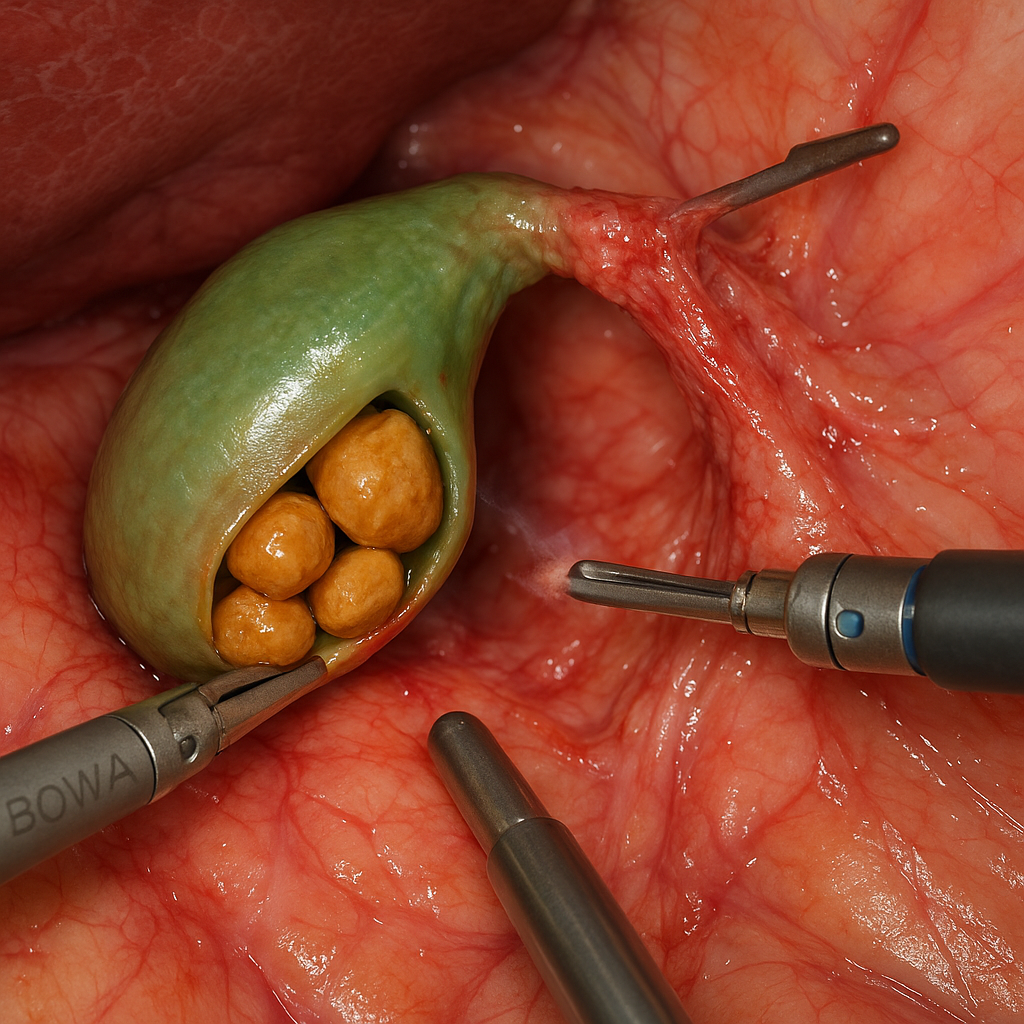

General & Laparoscopic Surgery